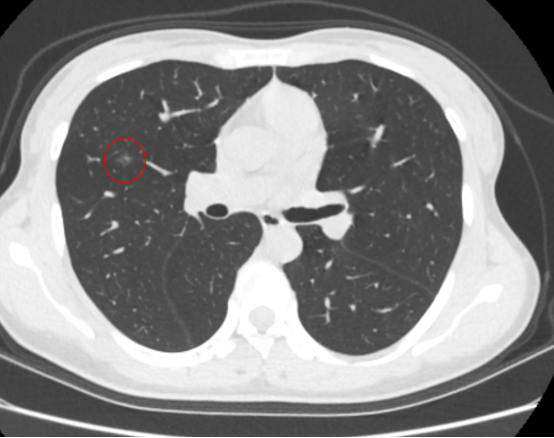

图片

图中红圈内提示术后热消融区完全覆盖原病灶

整个手术过程中王女士无明显不适,术后2小时即可下床正常活动,现已康复出院。